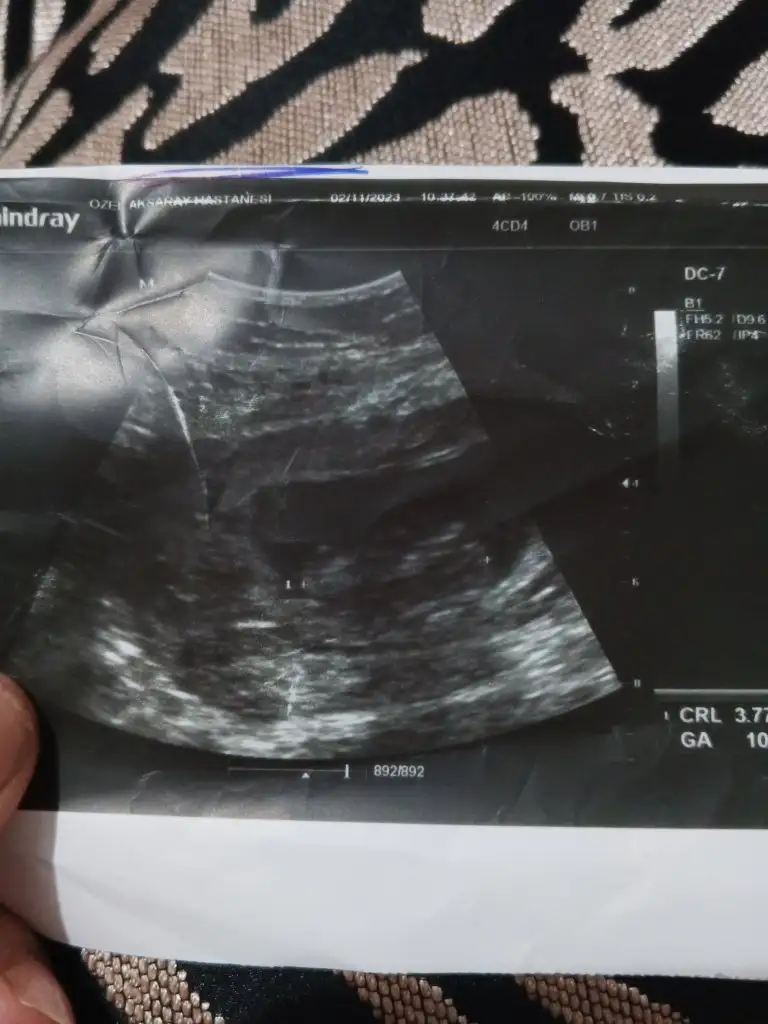

Sevde49 gönderdim bu resim geçen ayın... Dünkü doktor kontrolü ntrolunde çekilen resimleride attım bakarmisiniz sayfamda Allah rızası için

Eklentiler

• 17023915885283296783895134072047.webp

17023915885283296783895134072047.webp

39,9 KB · Görüntüleme: 152